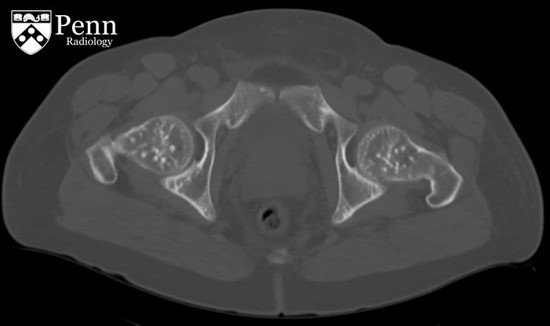

病史 男性,52岁,主诉腹部疼痛伴不明原因菌血症;患者有慢性肾病史。

腹盆CT图像如下

1.CT显示骨密度病变呈不均匀分布?(单选)

4.下面哪个是骨病变最可能的病因?(单选) 转移性肾细胞肾癌 转移性前列腺癌 骨斑点症 纹状骨病 肥大细胞增多症

5.以上骨病变的异常发生在骨的哪个部位?(单选)